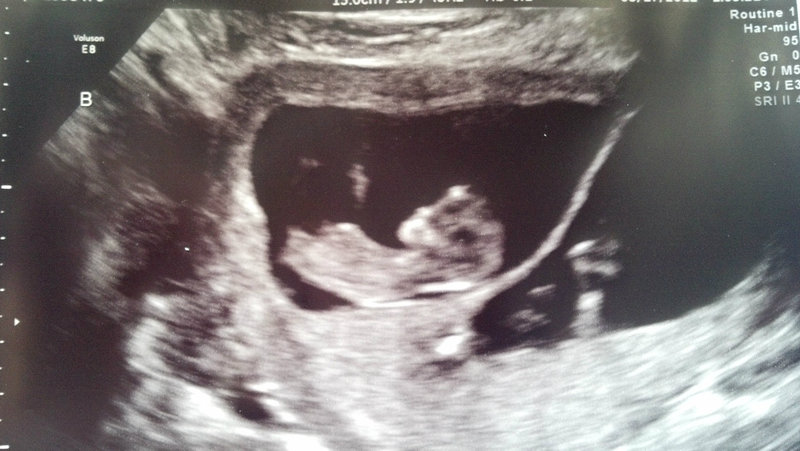

Attachment 3158

BABY A